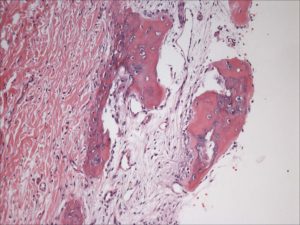

Tristan Project-Initial Pathology Report-Osteoma Cutis